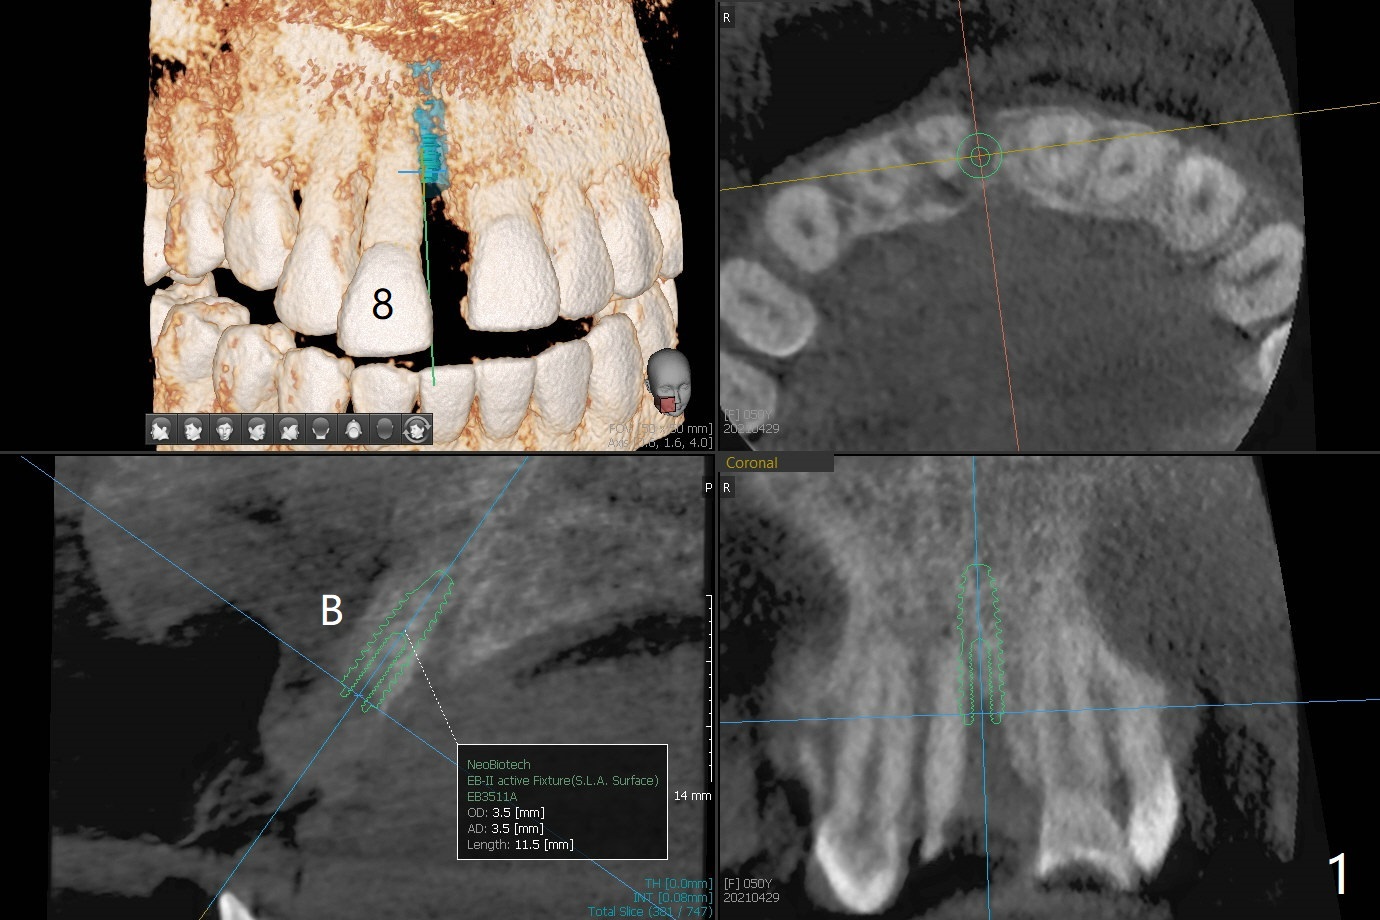

A 50-year-old woman complains of #8 buccodistal shifting (Fig.1,2). Conduct occlusal equilibrium until the affected tooth returns to its normal position. Trim the crown shell of the extracted tooth subgingival to the tooth #9 as a temporary crown (Fig.3,4). The gap between the socket and the tooth shell will be filled with sticky bone and PRF and covered by periodontal or acrylic dressing. The palatal bone loss is also severe (Fig.5); PRF should cover the palatal defect following sticky bone with a hole over the abutment.